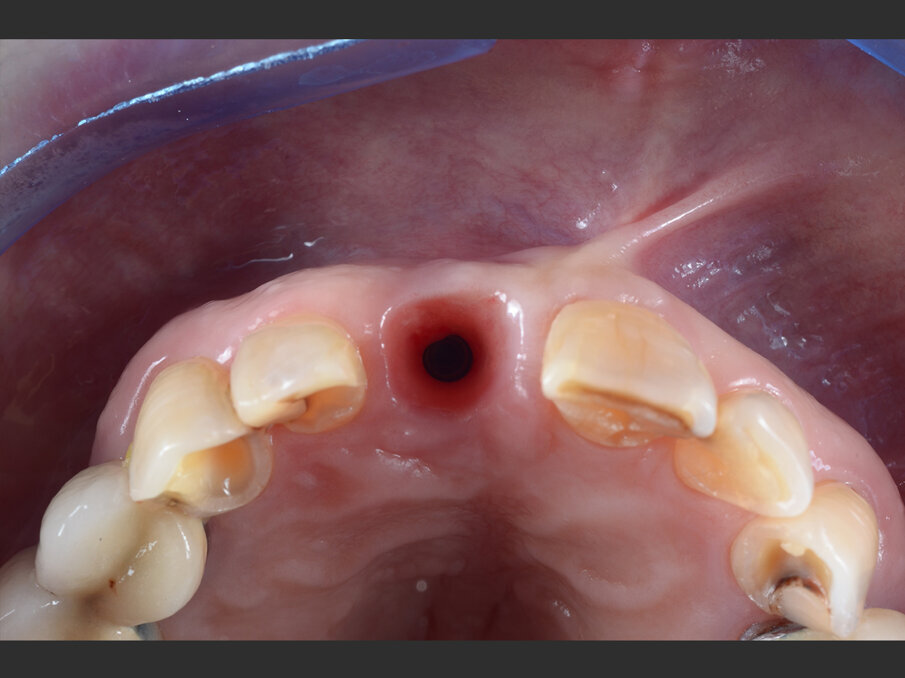

Fig. 7 - Valutazione clinica a 3 mesi dal posizionamento: l’impianto è ben integrato ed i tessuti molli sono stabili.

Figg. 9a, 9b - Acquisizione intraorale: tragitto transmucoso in visione occlusale.